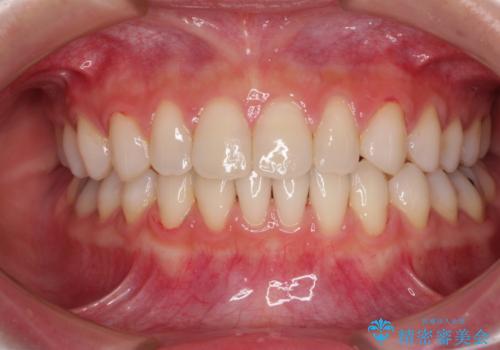

[ 歯を抜かないマウスピース矯正 ] 不揃いの目立つ前歯をきれいにしたい

担当医 大元洋佑